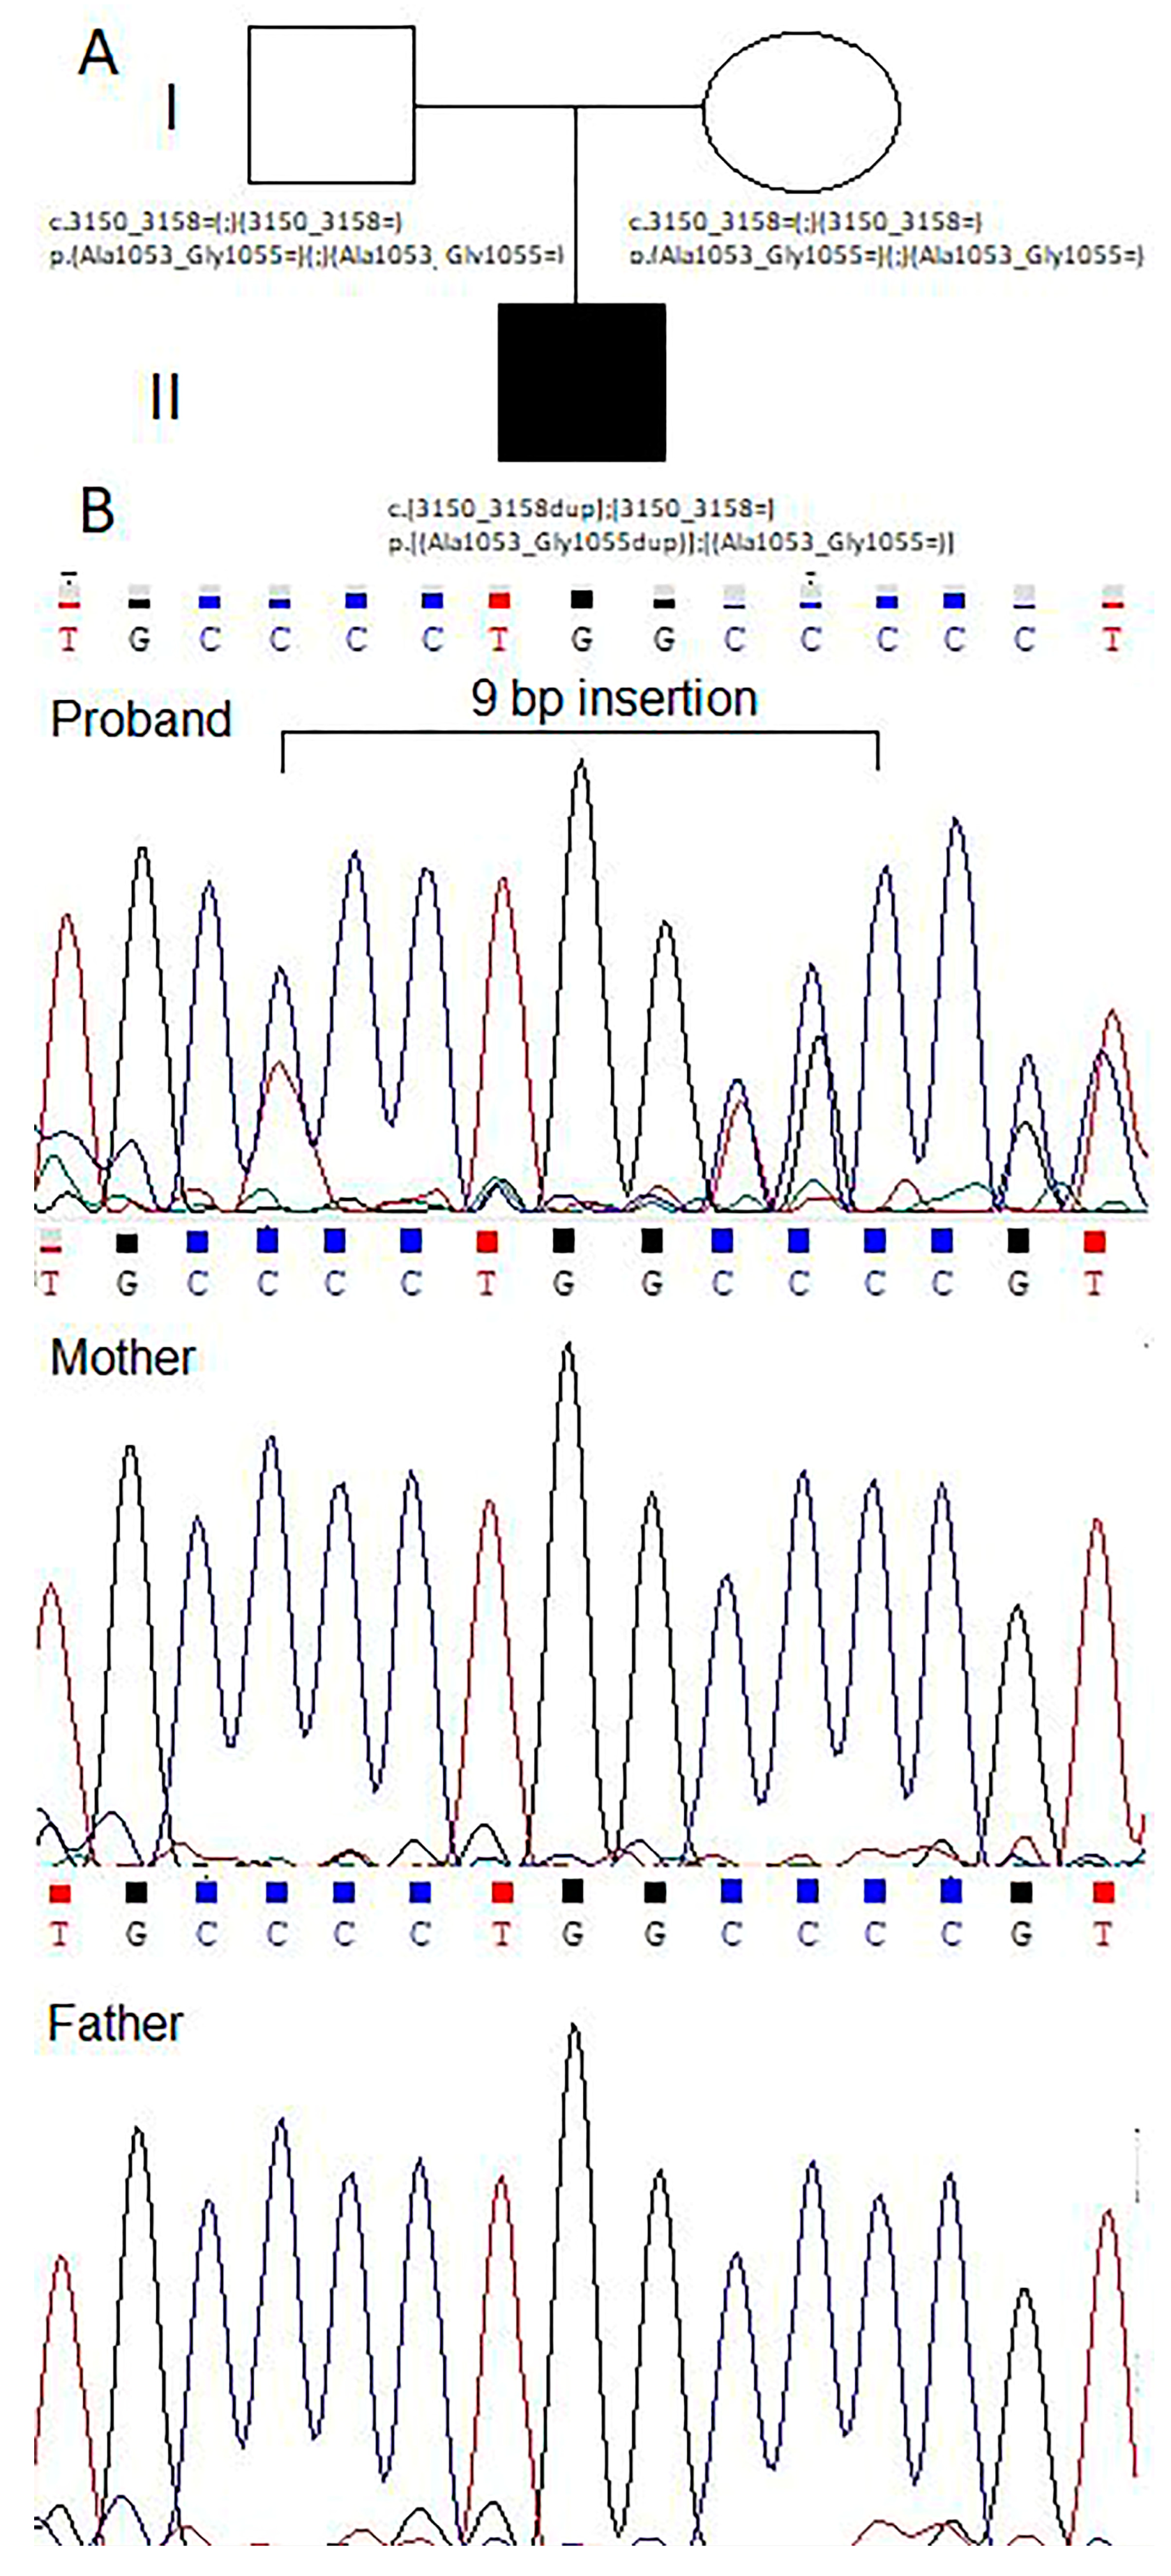

2.5. Genetic Counseling